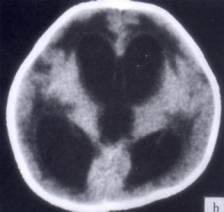

问题 病历摘要:??患者女性,10岁。结核性脑膜炎愈后8月,头痛伴恶心呕吐1周,并渐加重。体检:神清,精神差,反应迟钝,双眼底视神经乳头水肿,双眼外展差,余未见明显异常。 侧脑室-腹腔分流术后并发症包括下列哪些?

选项 A.分流管堵塞 B.分流过度 C.分流不足 D.硬膜下积液 E.感染 F.硬膜下血肿 G.癫痫

答案 ABCDEFG

解析 ABCDEFG